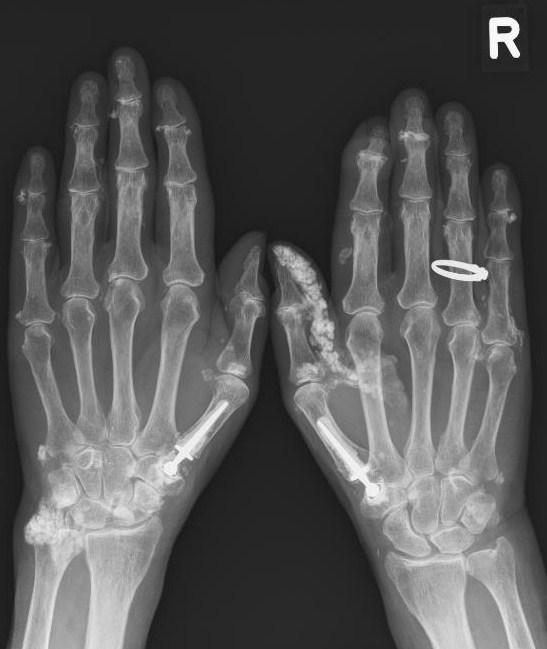

Een 81-jarige vrouw presenteerde zich met sinds enkele jaren bestaande, progressieve pijn, stijfheid, zwelling en een doof gevoel van de rechter duim. In 1979 had zij beiderzijds een duimbasisprothese (CMC-1) gekregen. Ze gaf tevens aan dat ze zich vaak verslikte en dat de passage van voedsel stagneerde. Daarbij had patiënte klachten passend bij het fenomeen van Raynaud. Bij lichamelijk onderzoek zagen wij een forse verdikking aan de gehele buigzijde van de duim. Buigen van de duim was niet mogelijk en zeer pijnlijk. De ulnaire zijde van de linker pols en beide olecrani waren gezwollen en gevoelig.